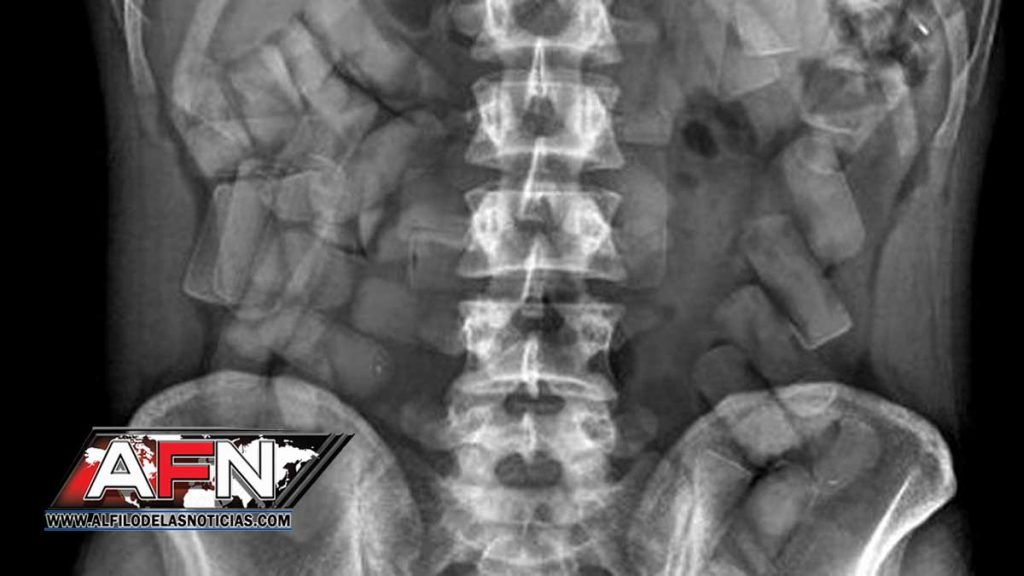

Posteriormente, y en presencia de un fiscal, se confirmó la presencia de imágenes sospechosas en su estómago, por lo que fue trasladado de inmediato al Hospital Central de las Fuerzas Armadas, donde tras varios días expulsó 99 bolsitas de la sustancia, con un peso preliminar de 1.2 kilogramos.